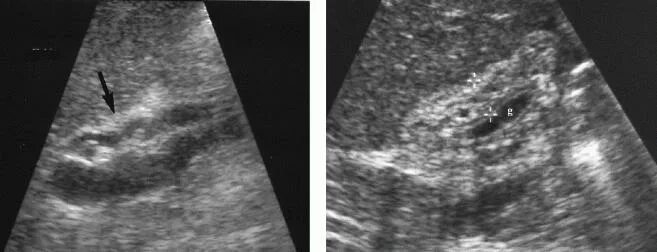

Можно вылечить полип желчного пузыря